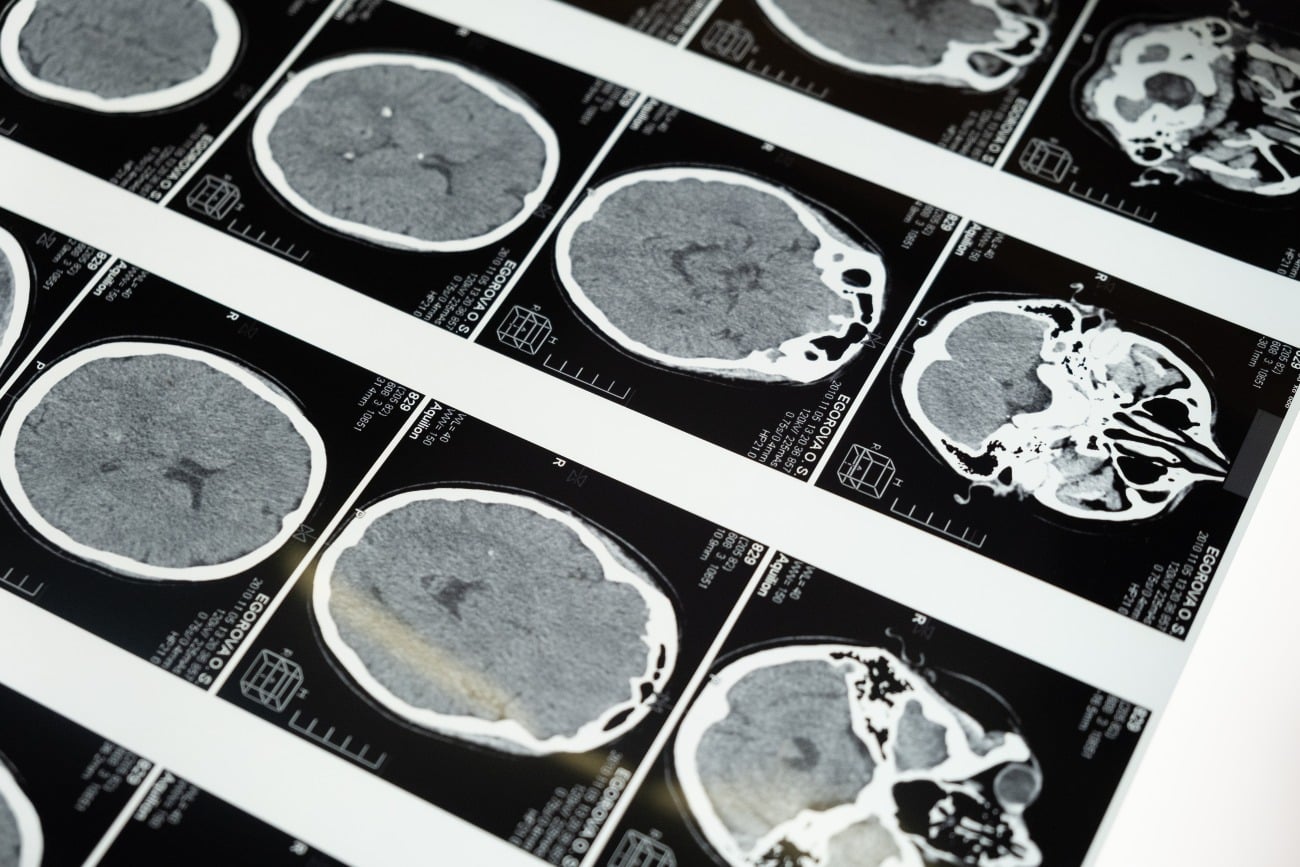

What Does Drug Use Do to the Brain?

brain scans